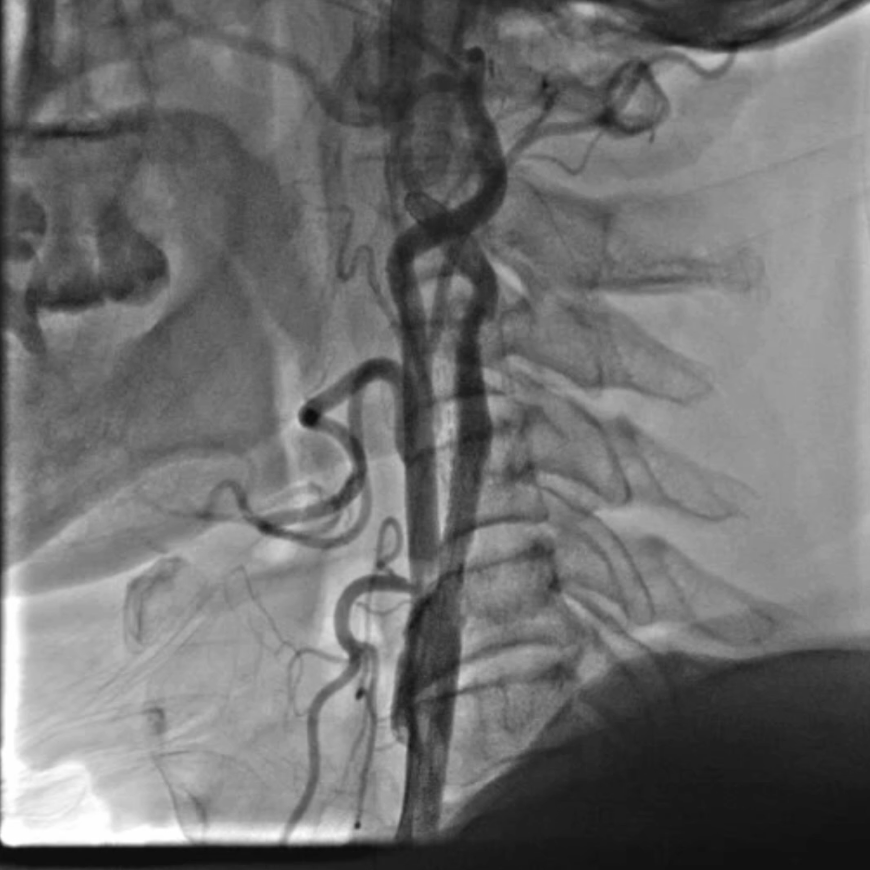

通路建立:精准操作减少血管损伤

穿刺与鞘管置入:局麻下穿刺右侧桡动脉,置入6F动脉鞘;

导管塑形与定位:使用SIMMONS导管选择左侧颈总动脉,操作时需轻柔(避免导管头端触碰血管壁导致斑块脱落),通过“反八字”塑形可精准对接左侧颈总动脉,导管弯部挂于颈动脉分叉处提供稳定支撑;

长鞘置入:在左前斜位透视下送入90cm长鞘,全程观察方向以避免阻力过大导致血管损伤

造影显示:支架膨胀良好,无需后扩张;

颅内血供:左侧颈内动脉血流通畅,因右侧闭塞,左侧成为全脑主要供血通路,血供恢复满意